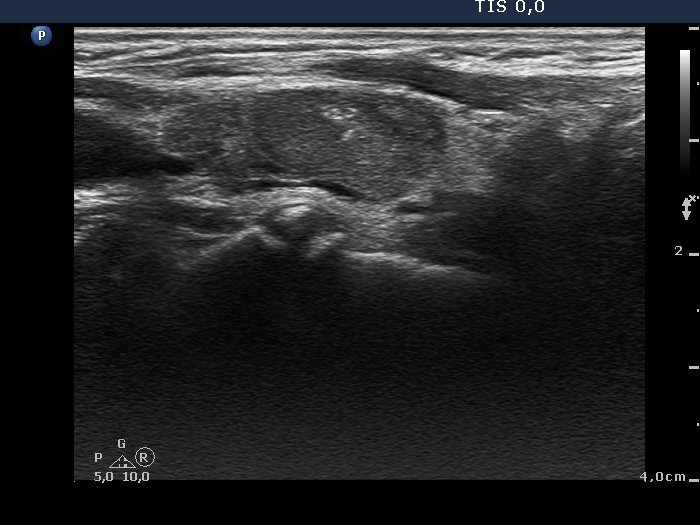

Graves' disease - case 169 (ultrasonographic picture 7)

Left lobe, another longitudinal view.